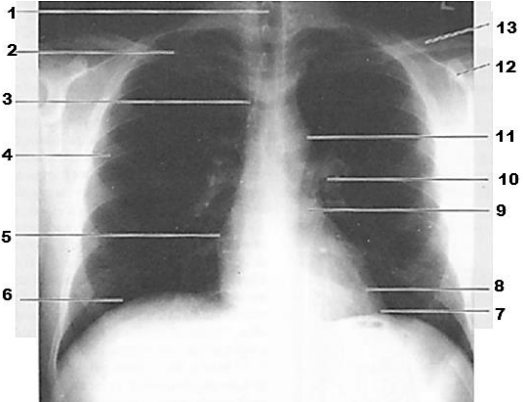

Dentre as causas de abdome agudo não traumático, as perfurações gastroduodenais estão entre as mais frequentes, seguindo-se as apendicites e as obstruções intestinais. A perfuração é a complicação mais grave da úlcera péptica, sendo caracterizada pela rotura da lesão com saída do conteúdo digestivo. Em nosso meio, é responsável por 5 a 10% das cirurgias abdominais de urgência. O diagnóstico sugerido pela história clínica é confirmado na rotina de abdome agudo pela presença de em até 90% dos casos.